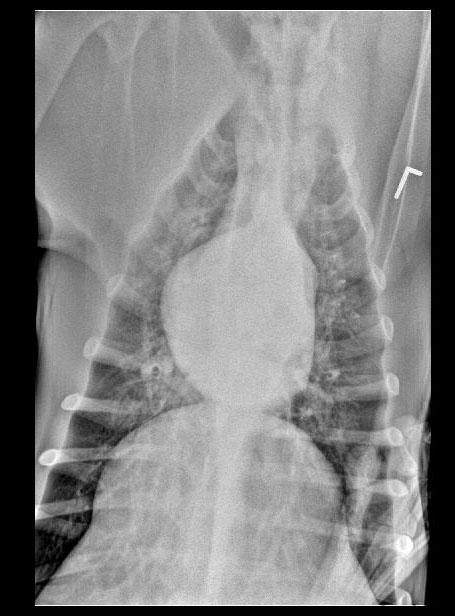

The patient is a canine Mastiff, male, 1 year old who was presented for surgery for the eye, however physical exam revealed muffled heart sounds. Radiographs revealed mass at the heart base.